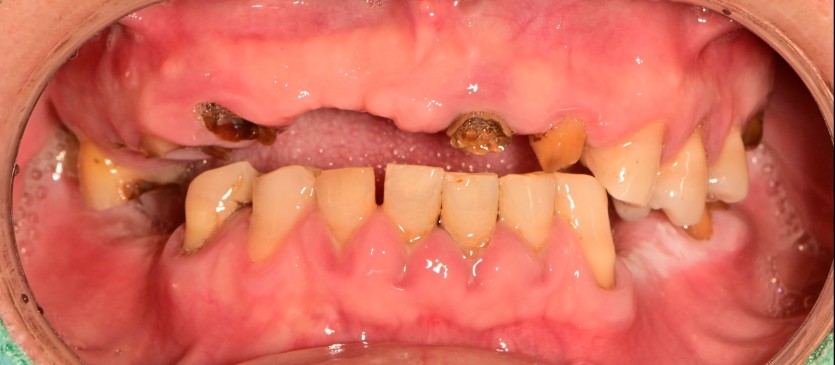

전체 임플란트 증례입니다.

18개의 임플란트로 완성하였습니다.